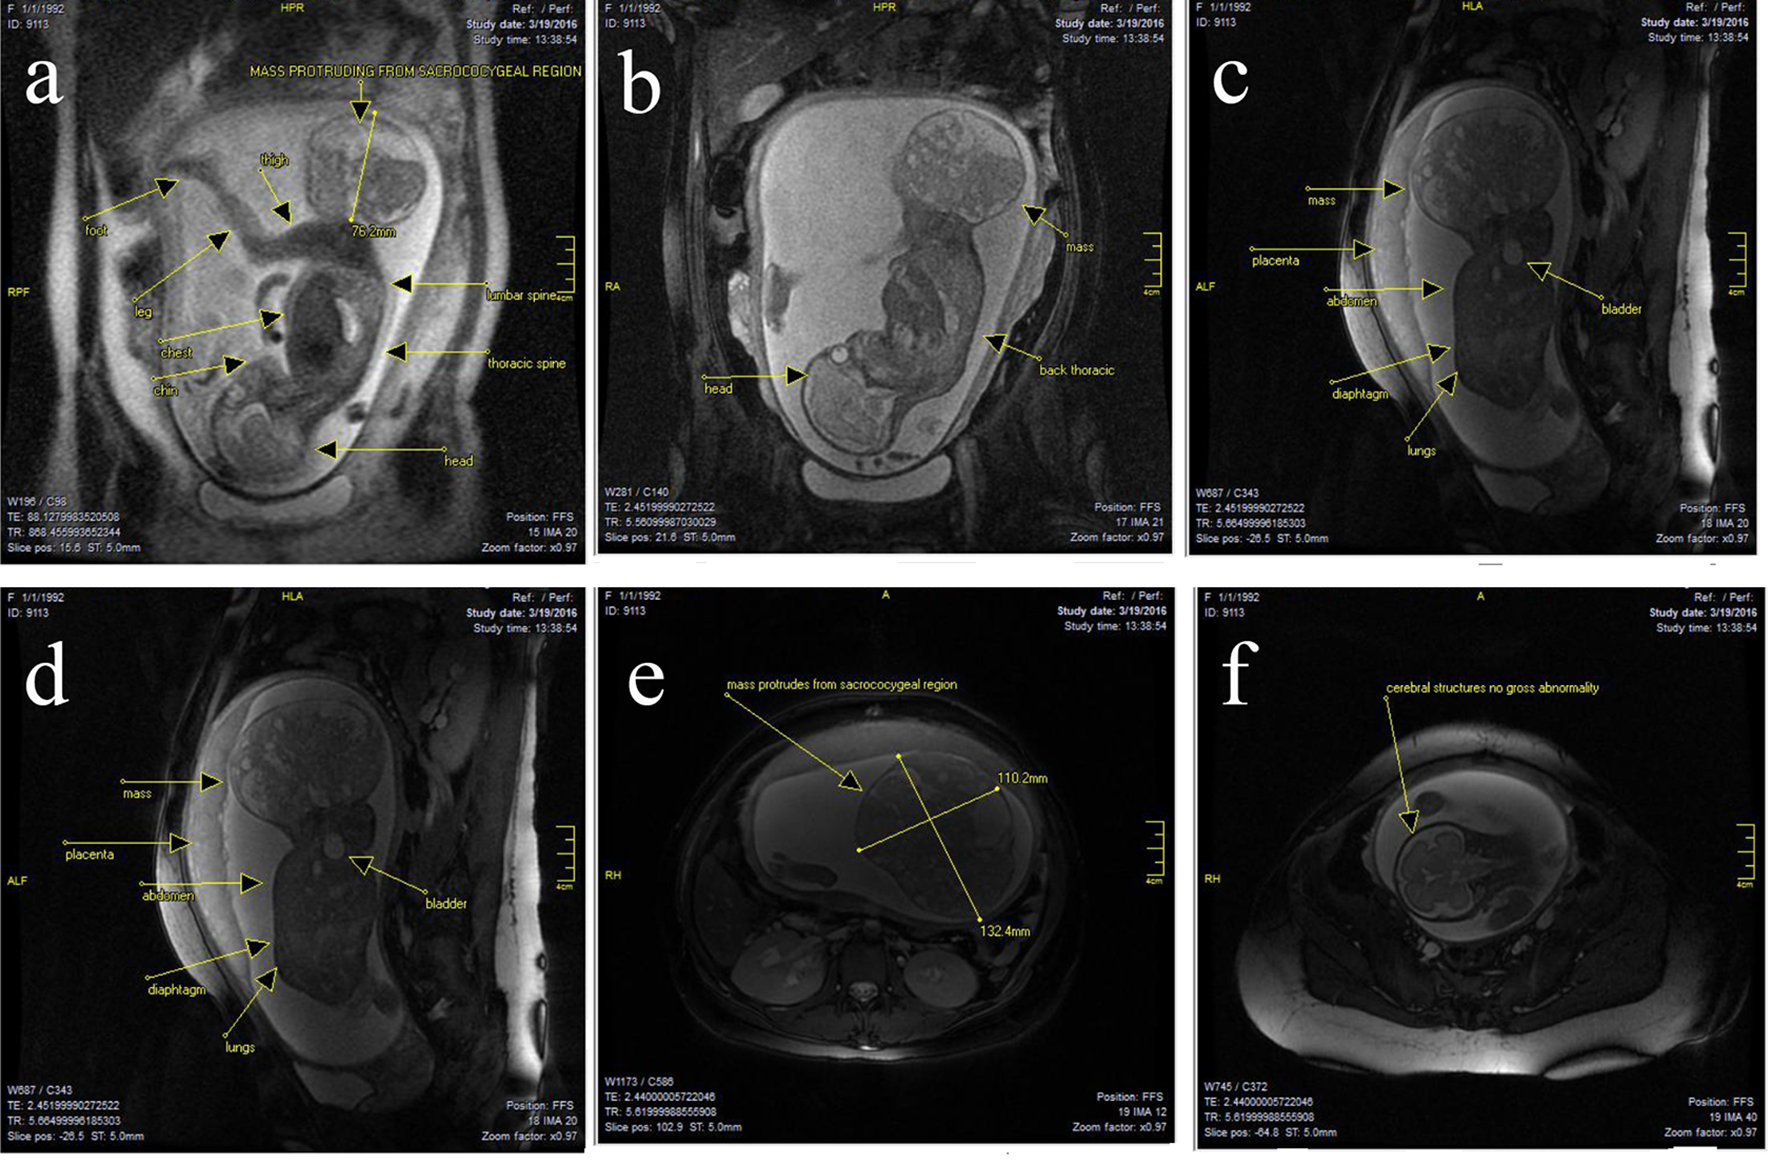

There was no obvious lumbar or thoracic spinal involvement. There was no gross intrapelvic or abdominal extension, and even sacrum and coccyx appeared deformed (Fig. 2a-e). The cervix was long at 40 mm and closed. The placenta was high and anterior. There was a normal three vessel cord without evident loops or knots. The amount of amniotic fluid was prominent. There was a single live intrauterine gestation. Current fetal lie was vertex, with spine to the mother’s left. At the level of the fetal brain, the degree of gyration and sulcation was as expected for the stated gestational age. No structural abnormalities were noted in the cerebral hemispheres. On T1-weighted images, myelination was as expected. The corpus callosum was present and normally formed. The brainstem and cerebellum including vermis had a normal appearance with transverse cerebellar diameter of 31 mm, in the expected range for gestational age. The craniocervical junction was unremarkable with no sign of Chiari or other malformation (Fig. 2f). The ocular globes had a normal and symmetrical appearance. The fetal face showed no midline cleft or other abnormality. The fetal spine was unremarkable. There was no sign of scoliosis or open neural tube defect. The fetal chest and abdomen showed visceral situs solidus with all the developed organs demonstrating proportional size and expected signal intensity on all sequences. Specifically, stomach, gallbladder, kidneys and urinary bladder were well seen and normal in appearance.

![]() Click for large image | Figure 2. (a-f) There was a large well-circumscribed mixed cystic solid oval mass, originating from right sacro-gluteal region and projecting into the amniotic cavity, 132 × 110 × 76 mm in size. The mass had a heterogenous appearance. There were T1 high signal suggesting fat component and there are T1 and T2 hypointense components suggesting calcific bony components. There was also T1 hypointense components consistent with cystic and fluid component. Findings suggested sacrococcygeal teratoma. There was no obvious lumbar or thoracic spinal involvement. There was no gross intrapelvic or abdominal extension. But sacrum and coccyx appeared deformed. At the level of the fetal brain, the degree of gyration and sulcation was as expected for the stated gestational age. No structural abnormalities were noted in the cerebral hemispheres. On T1-weighted images, myelination was as expected. The corpus callosum was present and normally formed. The brainstem and cerebellum including vermis had a normal appearance with transverse cerebellar diameter of 31 mm, in the expected range for gestational age. The craniocervical junction was unremarkable with no sign of Chiari or other malformation. |